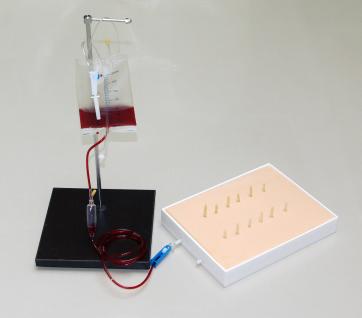

表面出血点止血训练模型

表面出血点止血训练模型